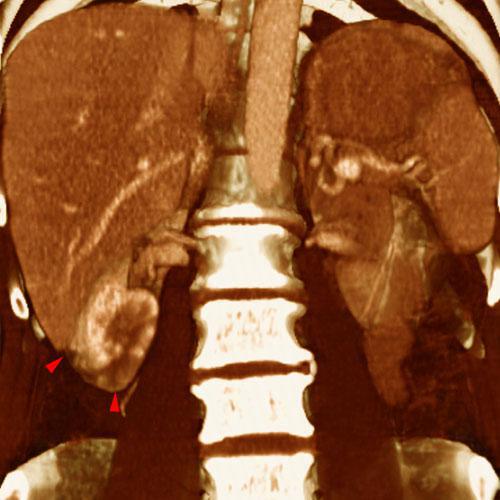

Infartos renales múltiples